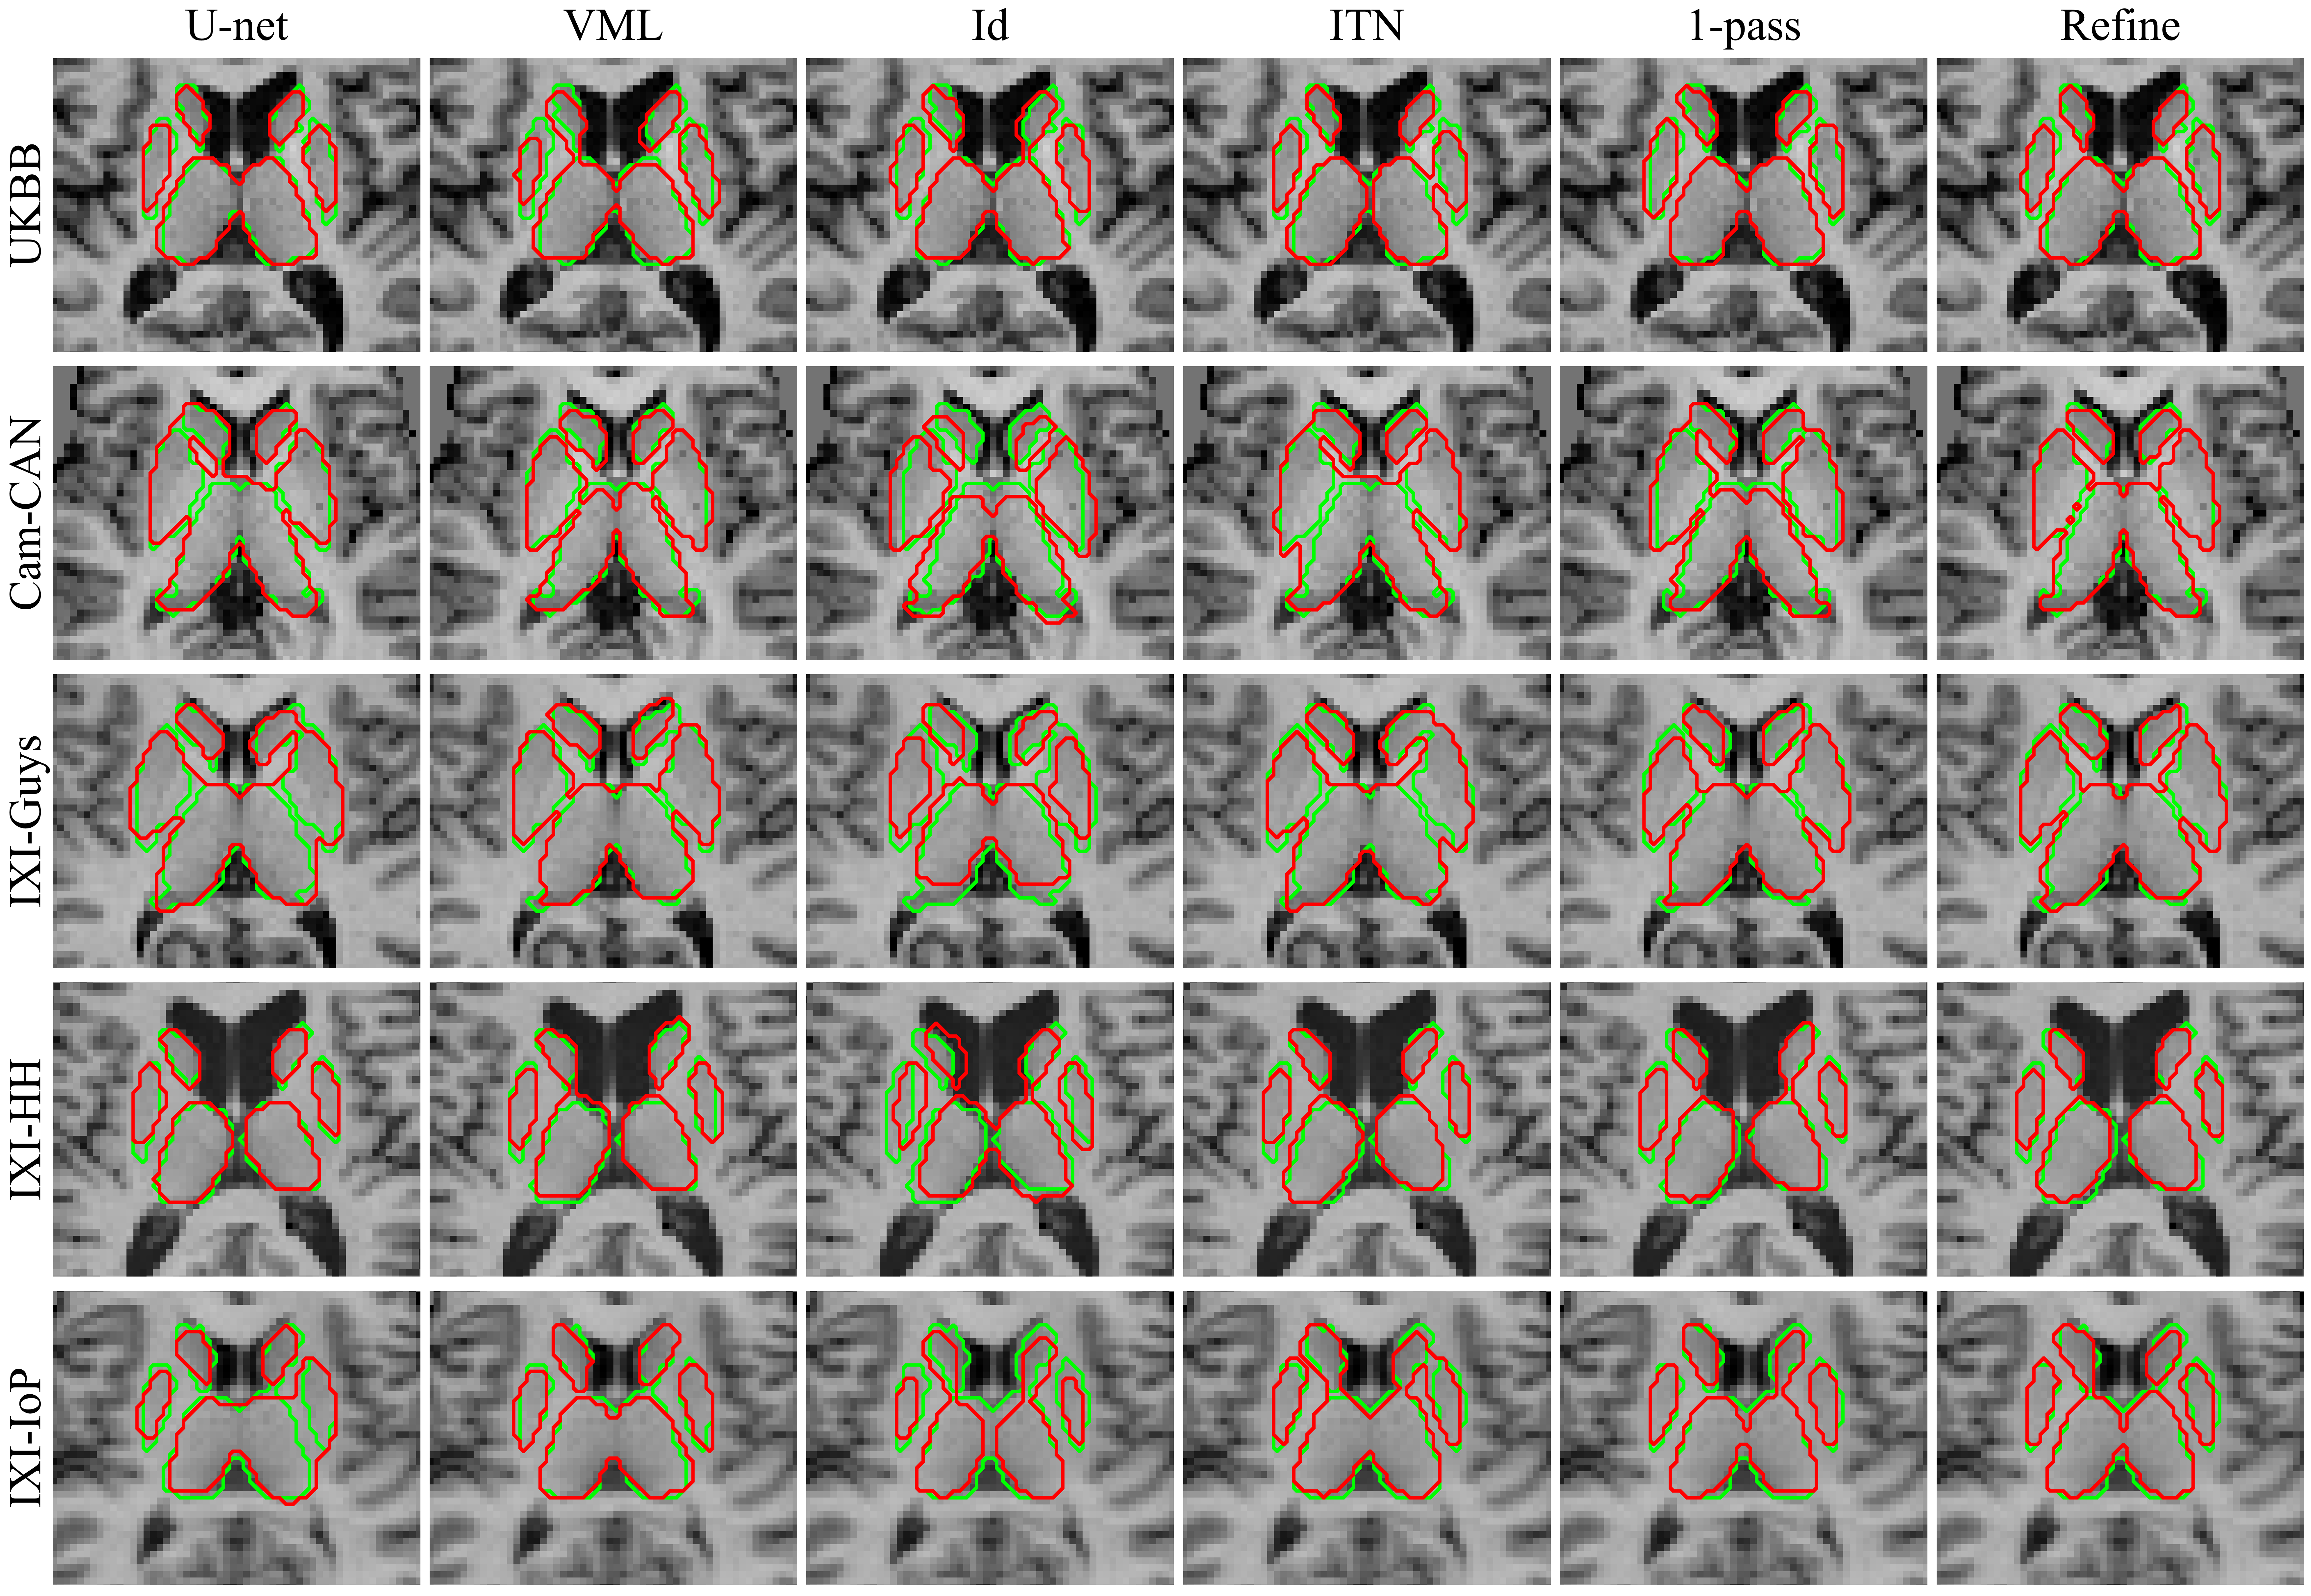

Experimental Results

The quantitative results are presented in Table 7 with a sensitivity analysis regarding the regularization weight in Fig. 15 with visual, qualitative results shown in Fig. 14. Overall, the U-net baseline performed quite well, out-performing the VML baseline on all datasets and performing similarly to the ITN. Atlas-ISTN performed the best on almost all test five datasets across all metrics, with the exception of HD on the Cam-CAN dataset. Test time refinement almost always improved over the ITN and 1-pass performance across all metrics as well. In Fig. 14, the U-net and ITN predictions often include false positives which connect neighbouring structures, most noticeably in rows 2 (Cam-CAN), 3 (IXI-Guys) and 5 (IXI-IoP). These errors are generally corrected with the VML, 1-pass and refinement results.

The VML model under-performed compared to the U-net and Atlas-ISTN models generally on all datasets across all metrics. The VML model did not generalize as well to other datasets, with the performance gap between VML and the other models increasing for datasets less similar to the training dataset. For the least similar dataset compared to the training data, IXI-IoP, the VML model DSC was 0.813 compared to 0.846, 0.839 and 0.862 for the Atlas-ISTN’s ITN, 1-pass and refinement results, respectively. The Atlas-ISTN 1-pass results out-performed the VML model across almost all metrics for all datasets, which could be attributed to the intermediate representation provided to the STN. Test time refinement of Atlas-ISTN also produced greater improvements over the ITN and 1-pass results for less similar datasets. On the UKBB dataset, the increase in DSC compared to the ITN and 1-pass were just and , respectively, while for IXI-IoP it was and , respectively.